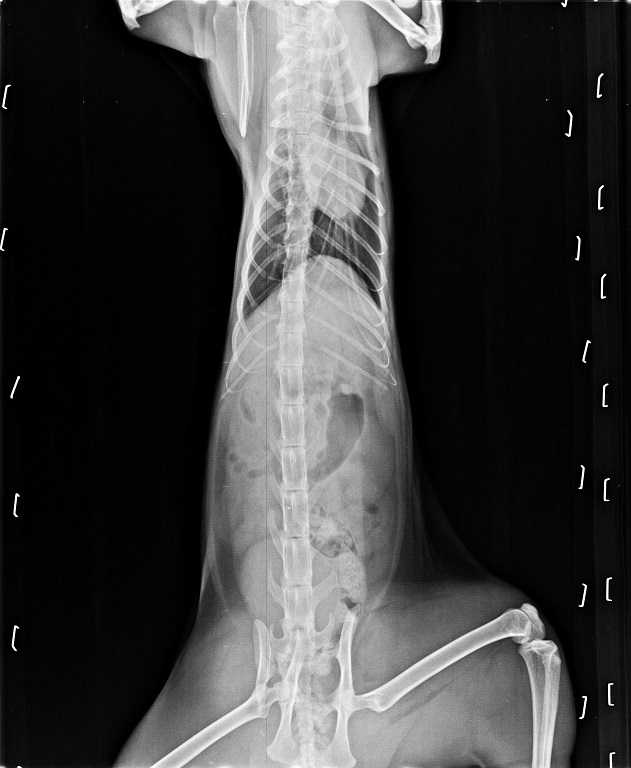

同同到了醫院後先鎮靜拍了X光照片檢查,

發現骨盆及兩條後腿都已經骨折,

且骨頭易位壓迫神經,

導致同同的後腿已經沒有知覺也沒辦法使力....